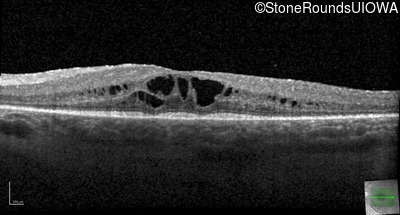

Optical Coherence Tomography - Right - 20/32 -1

Exemplar / OCT Stack

OCT Stack